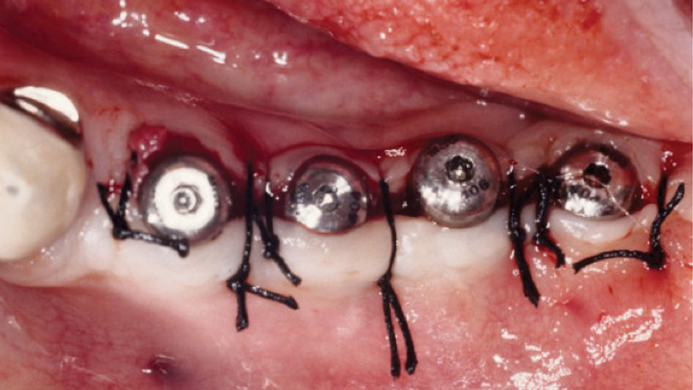

“Thin ridge expansion with minimally invasive surgery!

Use SmarThor & AnyRidge to place a wider diameter implant with minimal drilling after ridge splitting, even in thin ridge under 2mm! “

Clinical case: Ridge splitting technique using SmarThor + AnyRidge as expander

- Courtesy of Dr.Kwang-Bum Park, Korea -

Keywords

AnyRidge, ridge splitting, GBR, Dr. Kwang-Bum Park, mandibular posterior, SmartThor, Mega-Oss, thin ridge, bone regeneration

Products:

AnyRidge implant system. SmarThor, Mega-Oss